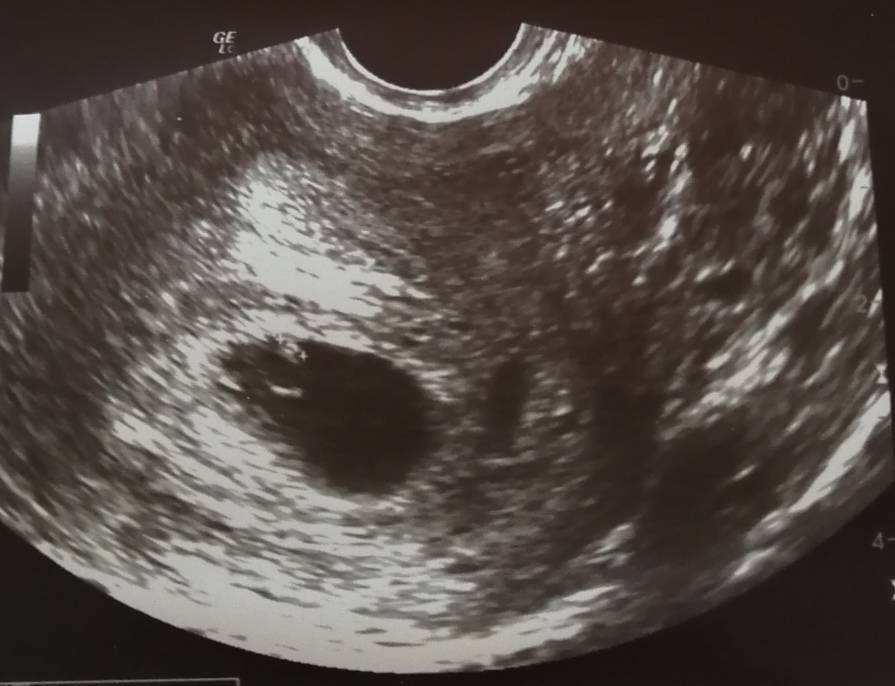

No to ja zacznę pierwsza. Wszystko ok! [emoji3526] Jest akcja serca, zero śladów jakichkolwiek krwawień. Niepotrzebna panika.